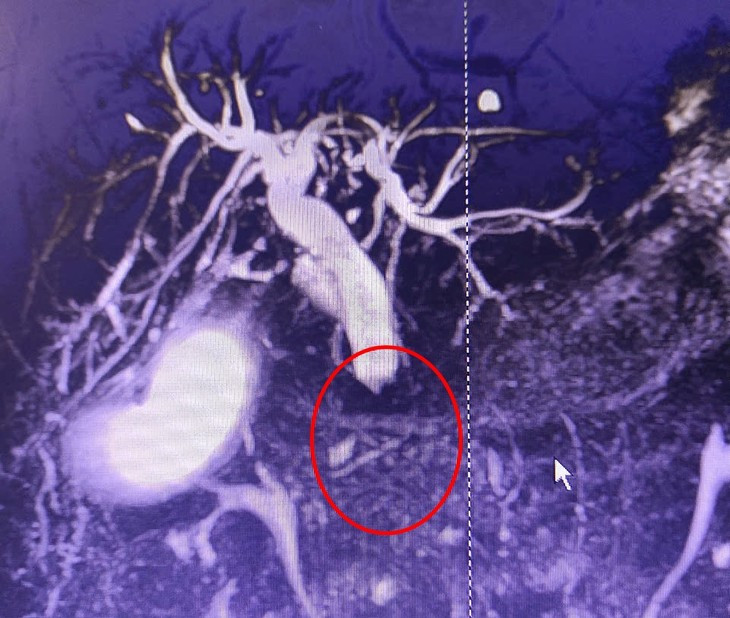

| Hình ảnh phần thấp ống mật chủ bị chít hẹp hoàn toàn do u - Ảnh BVCC |